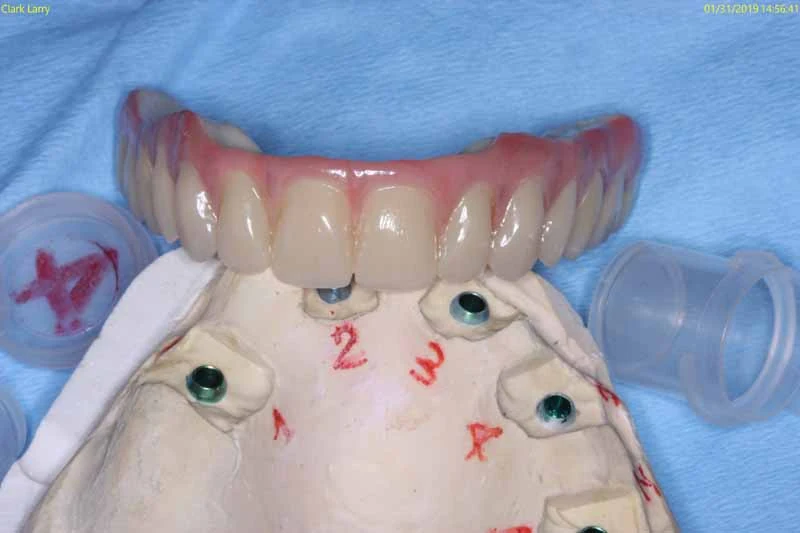

Once healed, the implant becomes firmly integrated with the jawbone and functions like a natural tooth. Patients can chew comfortably, speak clearly, and enjoy everyday foods without worrying about movement or irritation. Because of their strength and reliability, Bicon implants are frequently used in more advanced treatments at our practice, including full-mouth reconstruction and implant-supported dentures – providing a secure foundation for long-term oral health.

Dental Implant Gallery